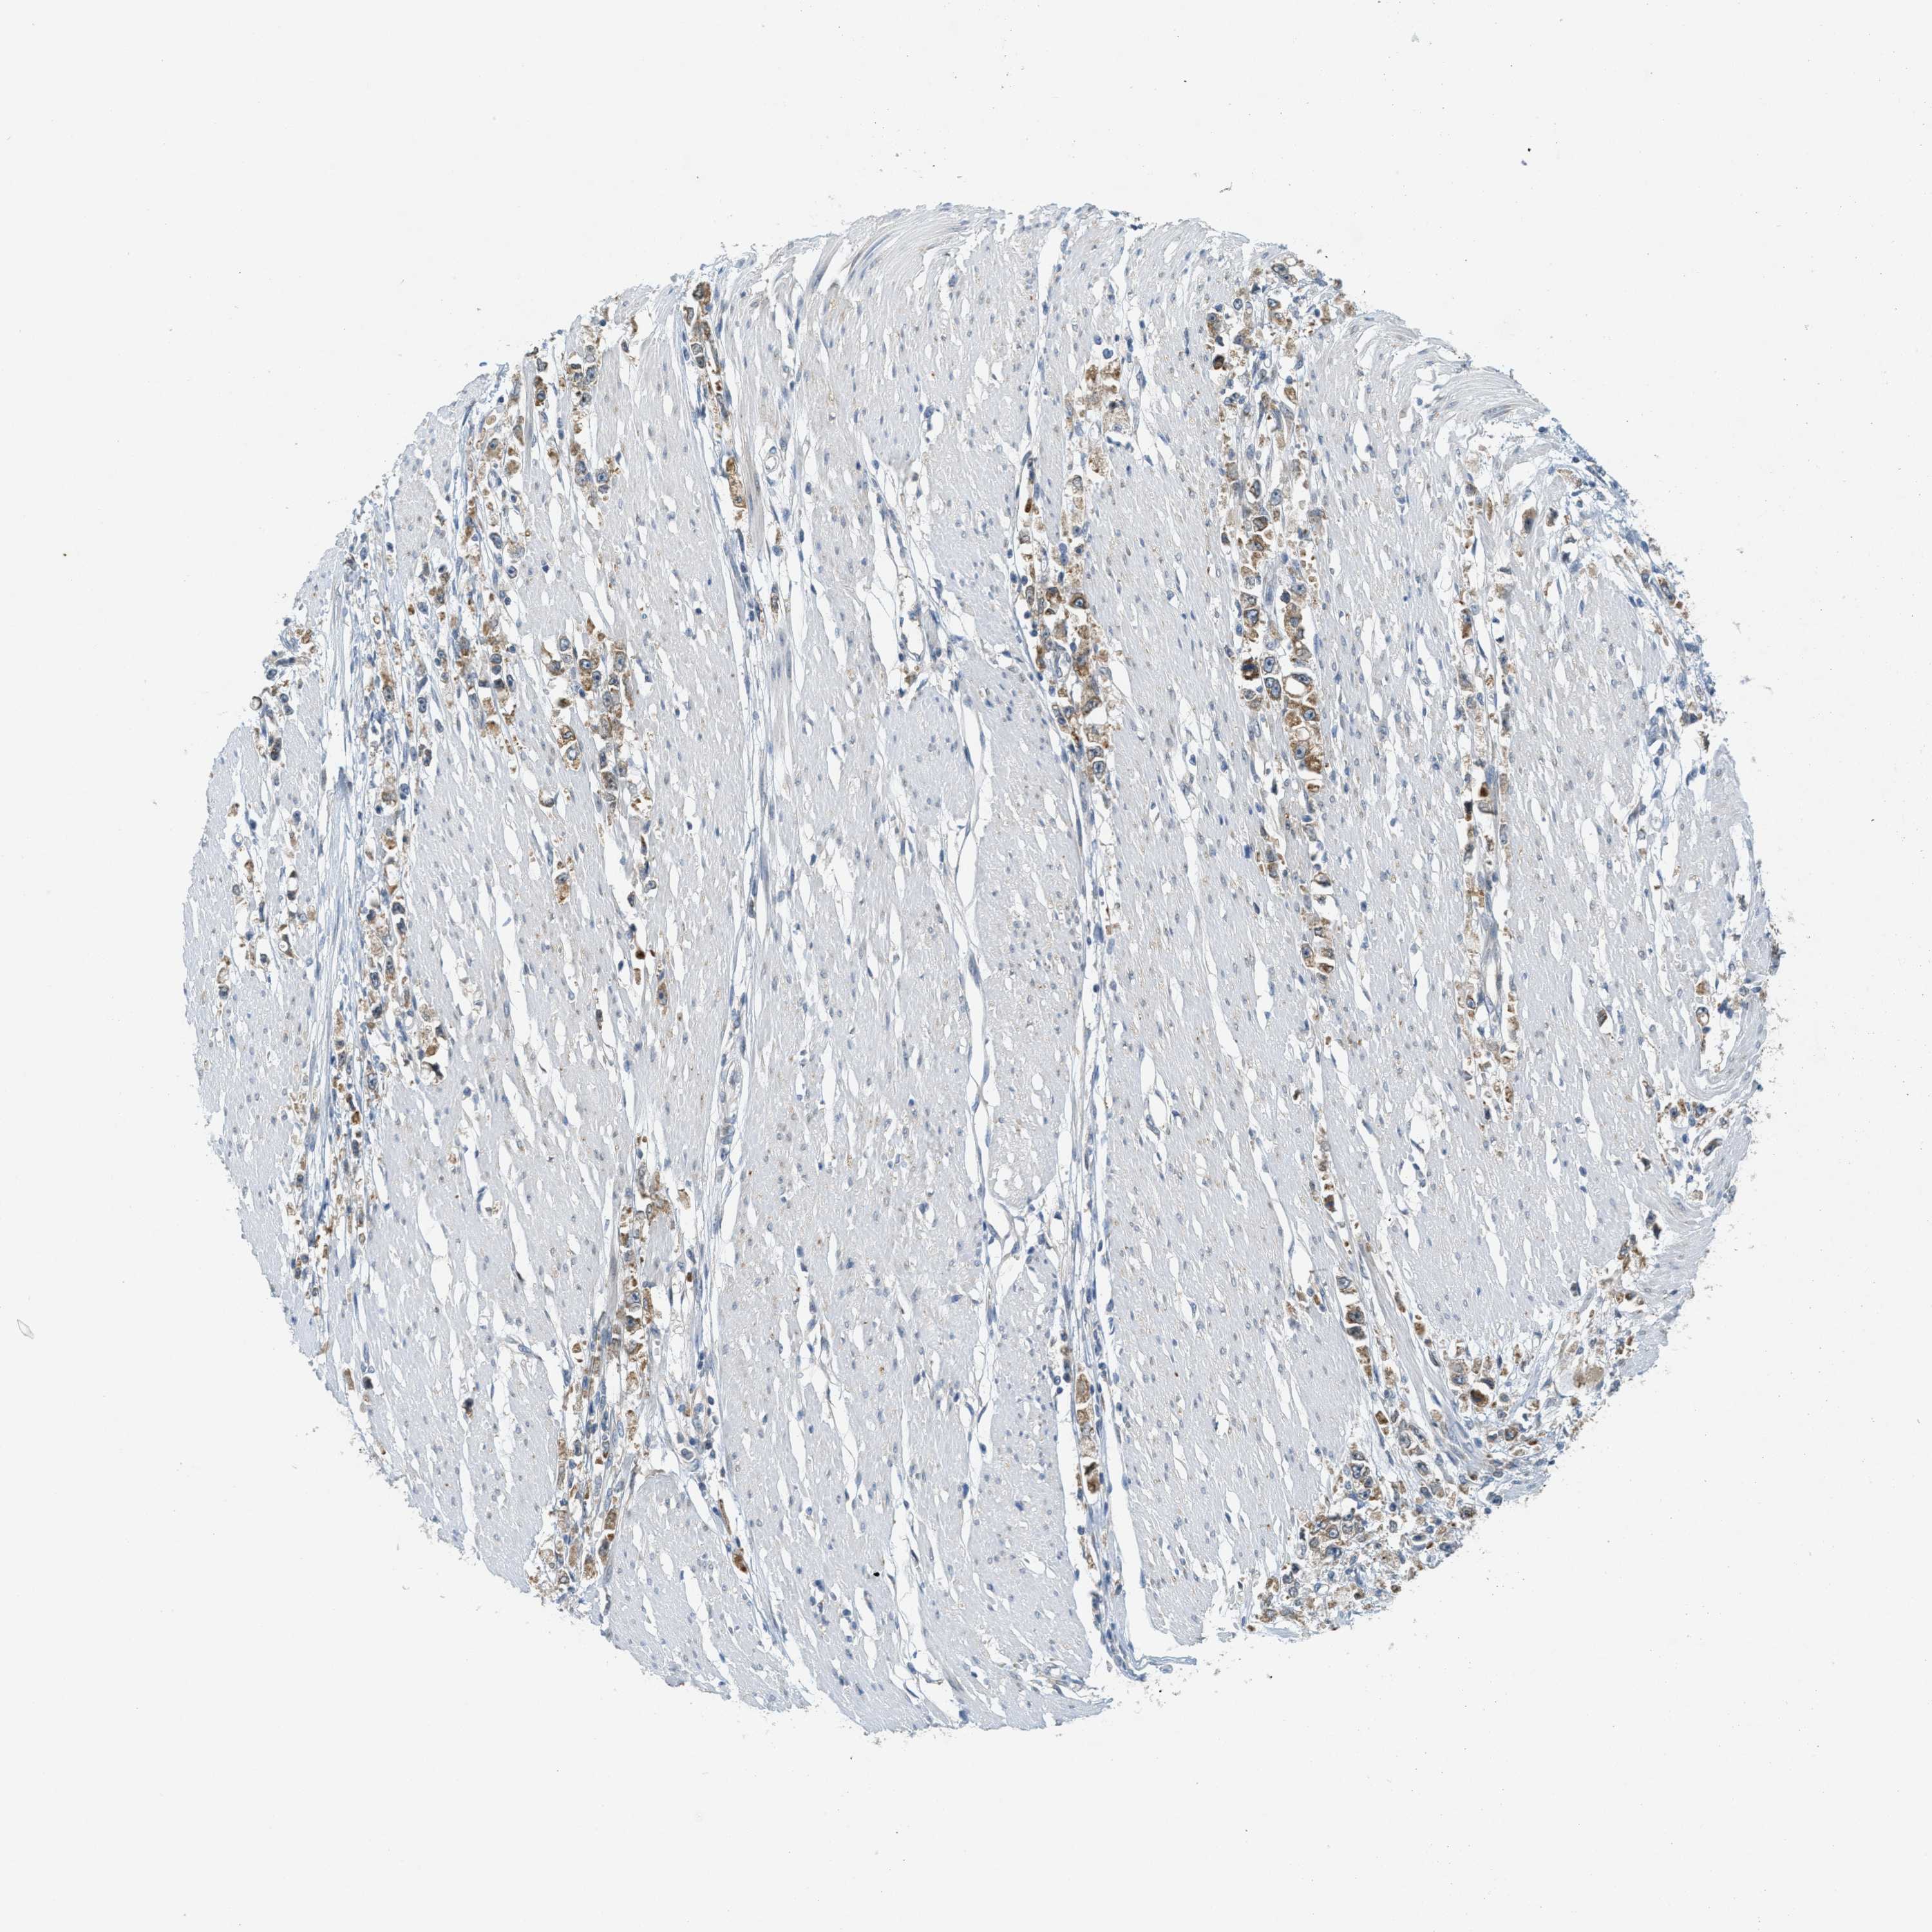

STOMACH CANCER - Protein expressioni

A mouse-over function shows sample information and annotation data. Click on an image to view it in a full screen mode. Samples can be filtered based on level of antibody staining by selecting one or several of the following categories: high, medium, low and not detected. The assay and annotation is described here.

Note that samples used for immunohistochemistry by the Human Protein Atlas do not correspond to samples in the TCGA dataset.

Antibody stainingi

Antibody staining in the annotated cell types in the current human tissue is reported as not detected, low, medium, or high, based on conventional immunohistochemistry profiling in selected tissues. This score is based on the combination of the staining intensity and fraction of stained cells.

Each image is clickable and will lead to virtual microscopy that enables deeper exploration of all samples and also displays staining intensity scores, fraction scores and subcellular localization as well as patient and tissue information for each sample.

Antibody HPA018002

Antibody HPA024071

Antibody CAB013470

Staining

High

Medium

Low

Not detected

Intensity

Strong

Moderate

Weak

Negative

Quantity

>75%

75%-25%

<25%

None

Location

Nuclear

Cytoplasmic/membranous

Cytoplasmic/membranous,nuclear

Adenocarcinoma, NOS

Adenocarcinoma, High grade